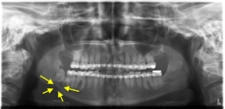

2. Cerrahi YöntemlerÇenenin yapısal bir problemi varsa, cerrahi müdahale gerekebilir. Aşağıdaki cerrahi yöntemler çenenin ileri alınmasında kullanılabilir: